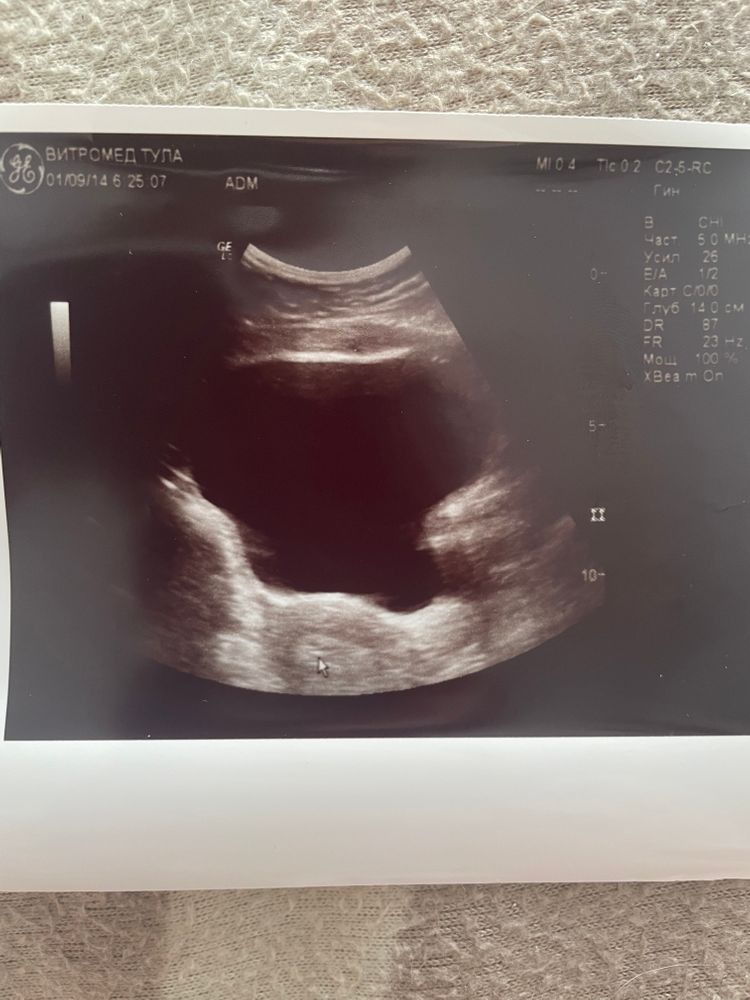

Анастасия, вы наверное не поняли… у меня вообще нет на узи ничего! Ни плодного яйца, ни внутри него чего то. Вообще. Ни сколько мм никаких круглешков на узи черных и тд!!! Просто матка по размерам беременная и пусто. Меня смотрела сама глава клиники. Опытная женщина. И она сказала-ничего. Плюс хгч упал на 2000. Я реалист! Лучше быстрее чтоб цикл начался и готовится к новому протоколу. у подруги у вашей значит и ПЯ было и внутри твм все эти ктр и жм. Просто СБ не нашли. А у меня вообще в матке никаких включений

А 1,3мм тогда что?

Анастасия, ну вы же понимаете что для 20дпп это капец какой маленький размер, если брать что это ПЯ. Ну какая то точка. Может ПЯ уже регрессировало и вот ч меня кровище и сгустки выпали. Может гематома была и вот рассосалась. Может еще что то. А может и ничего. Размеры малюсенькие, там не поймешь…

Поздравляю! Жаль фоточек не видно, кроме УЗИ. У меня вот тоже мышечные тики были, правда попозже, не только глаз, но и разные мышцы на руках и ногах дергались, неприятно было. Интересно почему так 🤔

Ivy, Изображение